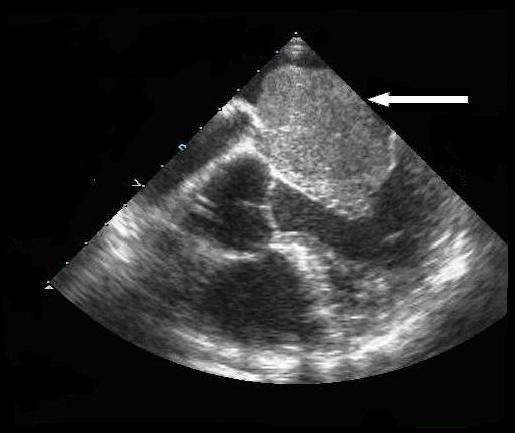

An 84-year-old Hispanic man presented with complaints of dizziness upon standing, and with no prior history of heart murmurs, syncope, shortness of breath, or chest pain. Physical examination revealed evidence of orthostatic hypotension and a soft grade 1/6 systolic murmur at the left sternal border. A transthoracic echocardiogram revealed a large atrial myxoma occupying the majority of the left atrium, with the posterior border of the large atrial mass defined by eccentric mitral regurgitation identified during cardiac catheterization. Left atrial myxoma excision was performed, revealing a 7 x 6.5 x 4.5 cm atrial tumor attached to a 4 x 3 x 2 cm stalk of atrial septal tissue.

一名84岁的西班牙裔男性因站立时头晕就诊,既往无心脏杂音、晕厥、呼吸急促或胸痛病史。体格检查发现体位性低血压的体征以及左胸骨旁柔和的1/6级收缩期杂音。经胸超声心动图显示一个大的心房黏液瘤占据了左心房的大部分,心脏导管检查期间通过偏心二尖瓣反流确定了大心房肿物的后边界。进行了左心房黏液瘤切除术,切除了一个7×6.5×4.5 cm的心房肿瘤,该肿瘤附着于一块4×3×2 cm的房间隔组织蒂上。